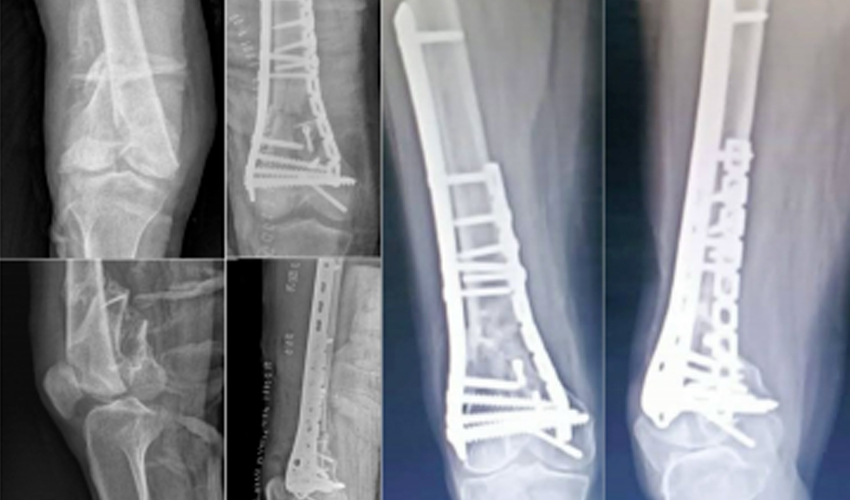

Preferred for displaced or unstable fractures. Includes lateral locking plates and dual-plate fixation techniques.

dual-plate-fixation-distal-femur-surgery-czmeditech

In regions such as Indonesia, Mexico, and the Middle East, the use of dual locking plate fixation for osteoporotic distal femoral fractures has become a preferred technique due to improved biomechanical stability and early mobilization outcomes.CZMEDITECH's products, including the Distal Femoral Lateral Locking Plate DCA24, have been successfully applied in international hospitals through.